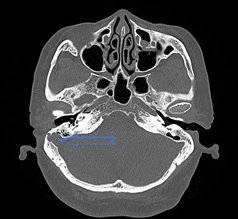

正常乙状窦在乳突后面会形成一较浅的骨性压迹,称为乙状窦沟。乙状窦沟前壁与骨性外耳道后壁的距离为10mm-14mm。

变异:按照标准,如果乙状窦向前凸入乳突后部,使骨性外耳道后壁与乙状窦前壁间距小于10mm,称为乙状窦前位。打个比方,就好像乙状窦这个“居民”不安分,往乳突后部这个“邻居家”靠近了许多。乙状窦憩室,是乙状窦壁向乳突气房或者颞骨皮质突出,乙状窦壁像个气球,局部出现了一个“小鼓包”。

正常乙状窦 乙状窦前位+乙状窦憩室